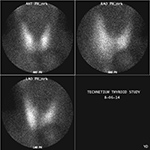

Thyroid imaging with pinhole collimator after the injection of free Tc-99m pertechnetate shows a rounded focal photopenic defect in the region of the left lower thyroid lobe caused by a nonfunctional photomultiplier tube. Focal intense activity seen in the right antecubital region and along the right lateral abdominal wall on Tc-99m MDP scan is related to extravasation of radiopharmaceutical at the injection site with scatter of photons from the forearm to the abdominal wall (narrow angle scatter). Fused axial FDG PET-CT (B), PET axial (C), CT axial (D) and MIP PET (E) images demonstrate intensely FDG avid lymph node in the right axilla. Infiltration of FDG at the injection site in right antecubital fossa results in lymphoscintigraphy with FDG migrating to the regional nodal basin via the lymphatic ducts.

Figure 30D Figure 30E Figure 31

Figure 30C Figure 30E Figure 31

Fused axial FDG PET-CT (B), PET axial (C), CT axial (D) and MIP PET (E) images, demonstrate intensely FDG avid lymph node in the right axilla. Infiltration of FDG at the injection site in right antecubital fossa results in lymphoscintigraphy with FDG migrating to the regional nodal basin via the lymphatic ducts. Technetium 99m MDP whole body bone scan shows photopenic defect on the midline pelvis from the attenuation of a belt buckle.